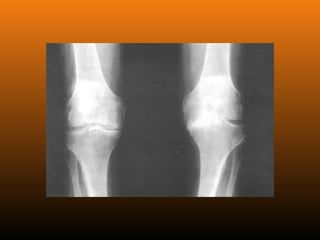

RADIOLOGIA

No início da doença não se observam anormalidades. Com seu

desenvolvimento, observam-se:

 Diminuição do espaço intra-articular

 Esclerose subcondral (eburnação)

 Osteófitos;

 Erosão e anquilose óssea (pseudocistos ósseos).

PATOLOGIA As alterações patológicaspresentes nas articulações com osteoartrite incluem a degradação da cartilagem articular, o espessamento do osso subcondral, a formação de osteófitos, graus variáveis de inflamação sinovial, degeneração de ligamentos no joelho, meniscos e hipertrofia da cápsula articular.